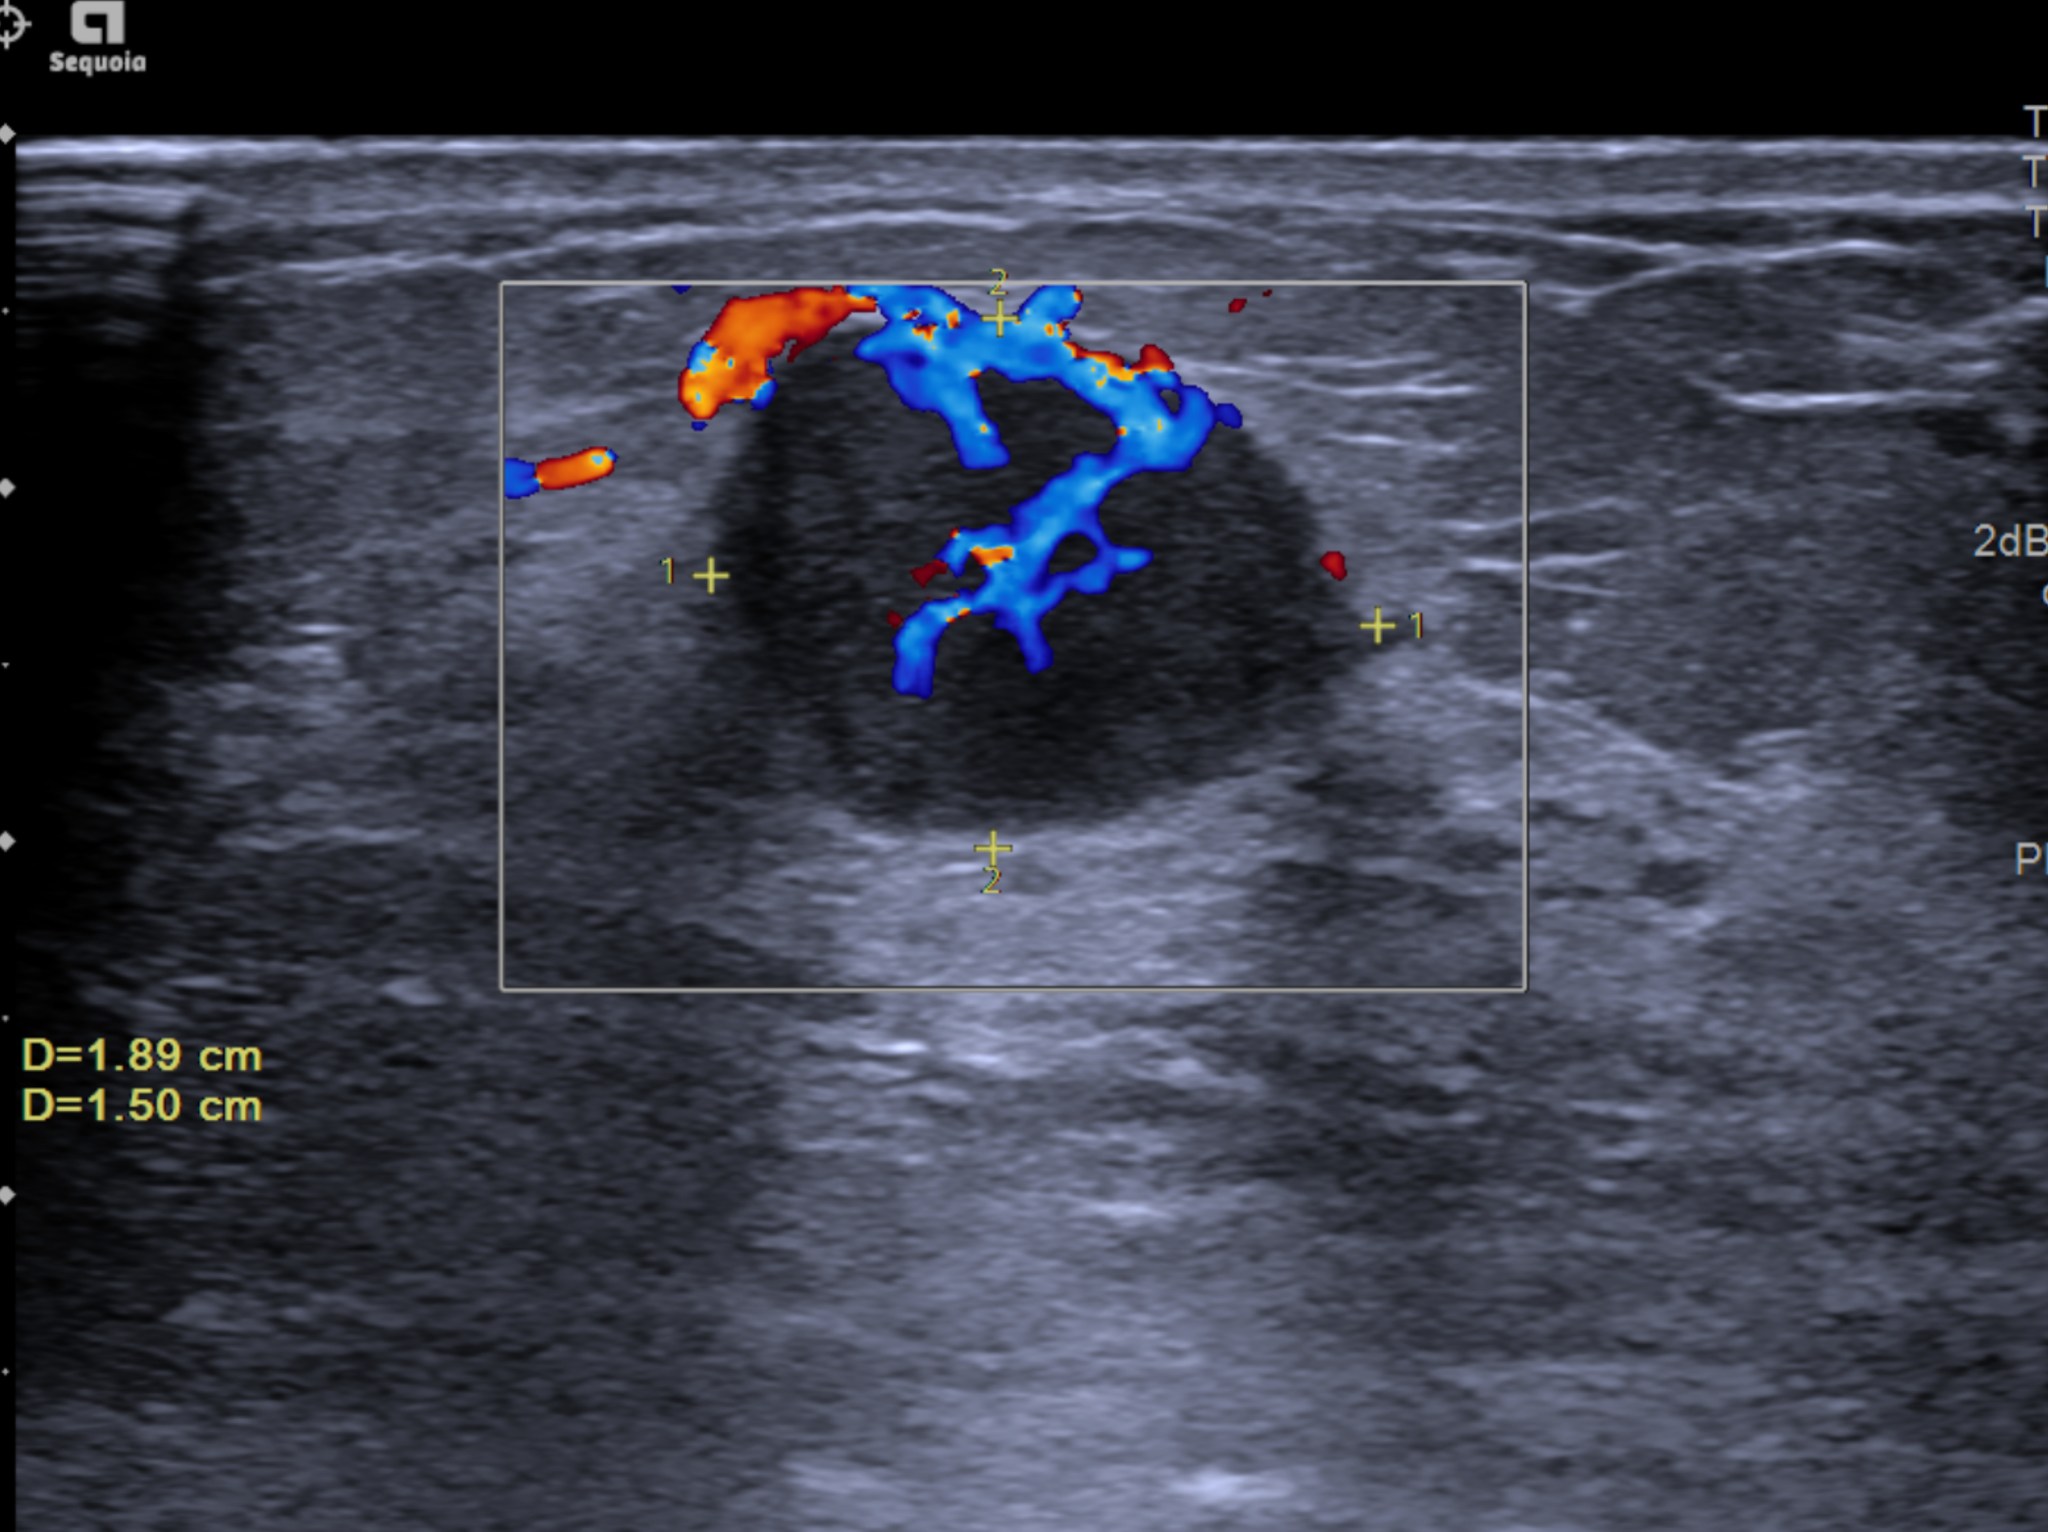

Sinh thiết vú dưới hướng dẫn siêu âm: Quy trình và lợi ích

Khi phát hiện có khối u hoặc bất thường ở tuyến vú qua thăm khám hoặc chẩn đoán hình ảnh, sinh thiết vú dưới hướng dẫn siêu âm là một phương...